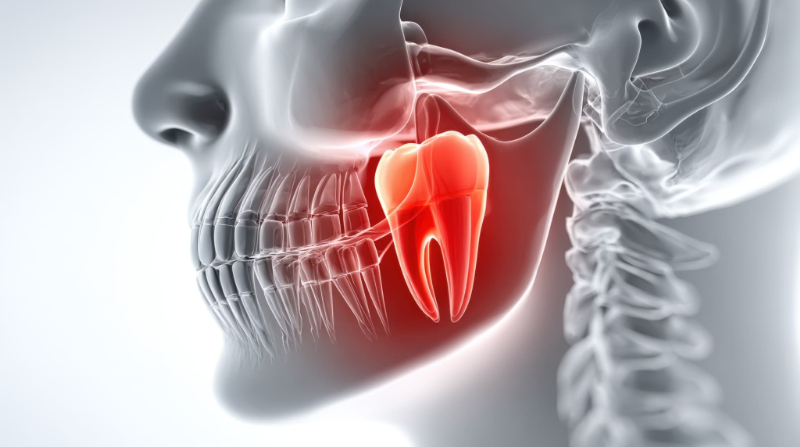

親知らずは、永久歯の中で最も奥に位置する歯で、正式には第三大臼歯と呼ばれます。上下左右にそれぞれ1本ずつあるとされ、最大で4本存在しますが、人によってはもともと存在しない場合もあります。

この歯は、食べ物をすりつぶす役割を持つ奥歯の一種ですが、現代の食生活や顎の大きさの変化により、ほかの歯と比べて扱いが難しい歯とされています。また、口の一番奥にあるため、自分では状態を確認しづらく、違和感やトラブルが起きて初めて気づくことも少なくありません。